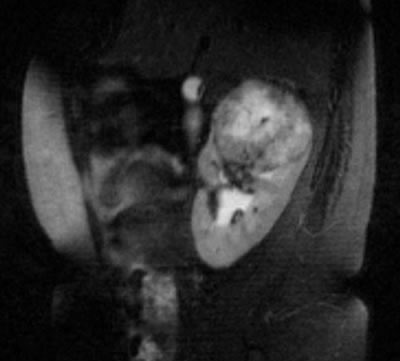

МРТ |

|

МРТ – регионарные лимфоузлы

увеличены до 15-17 мм в диаметре, в желчном пузыре

несколько камней с максимальным размером 6-7 мм